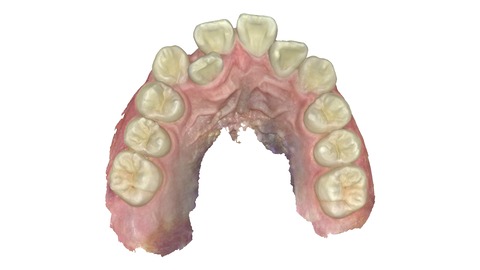

上の歯。引っ込んだ歯が歯並びの中に納まっている。

上の歯の比較